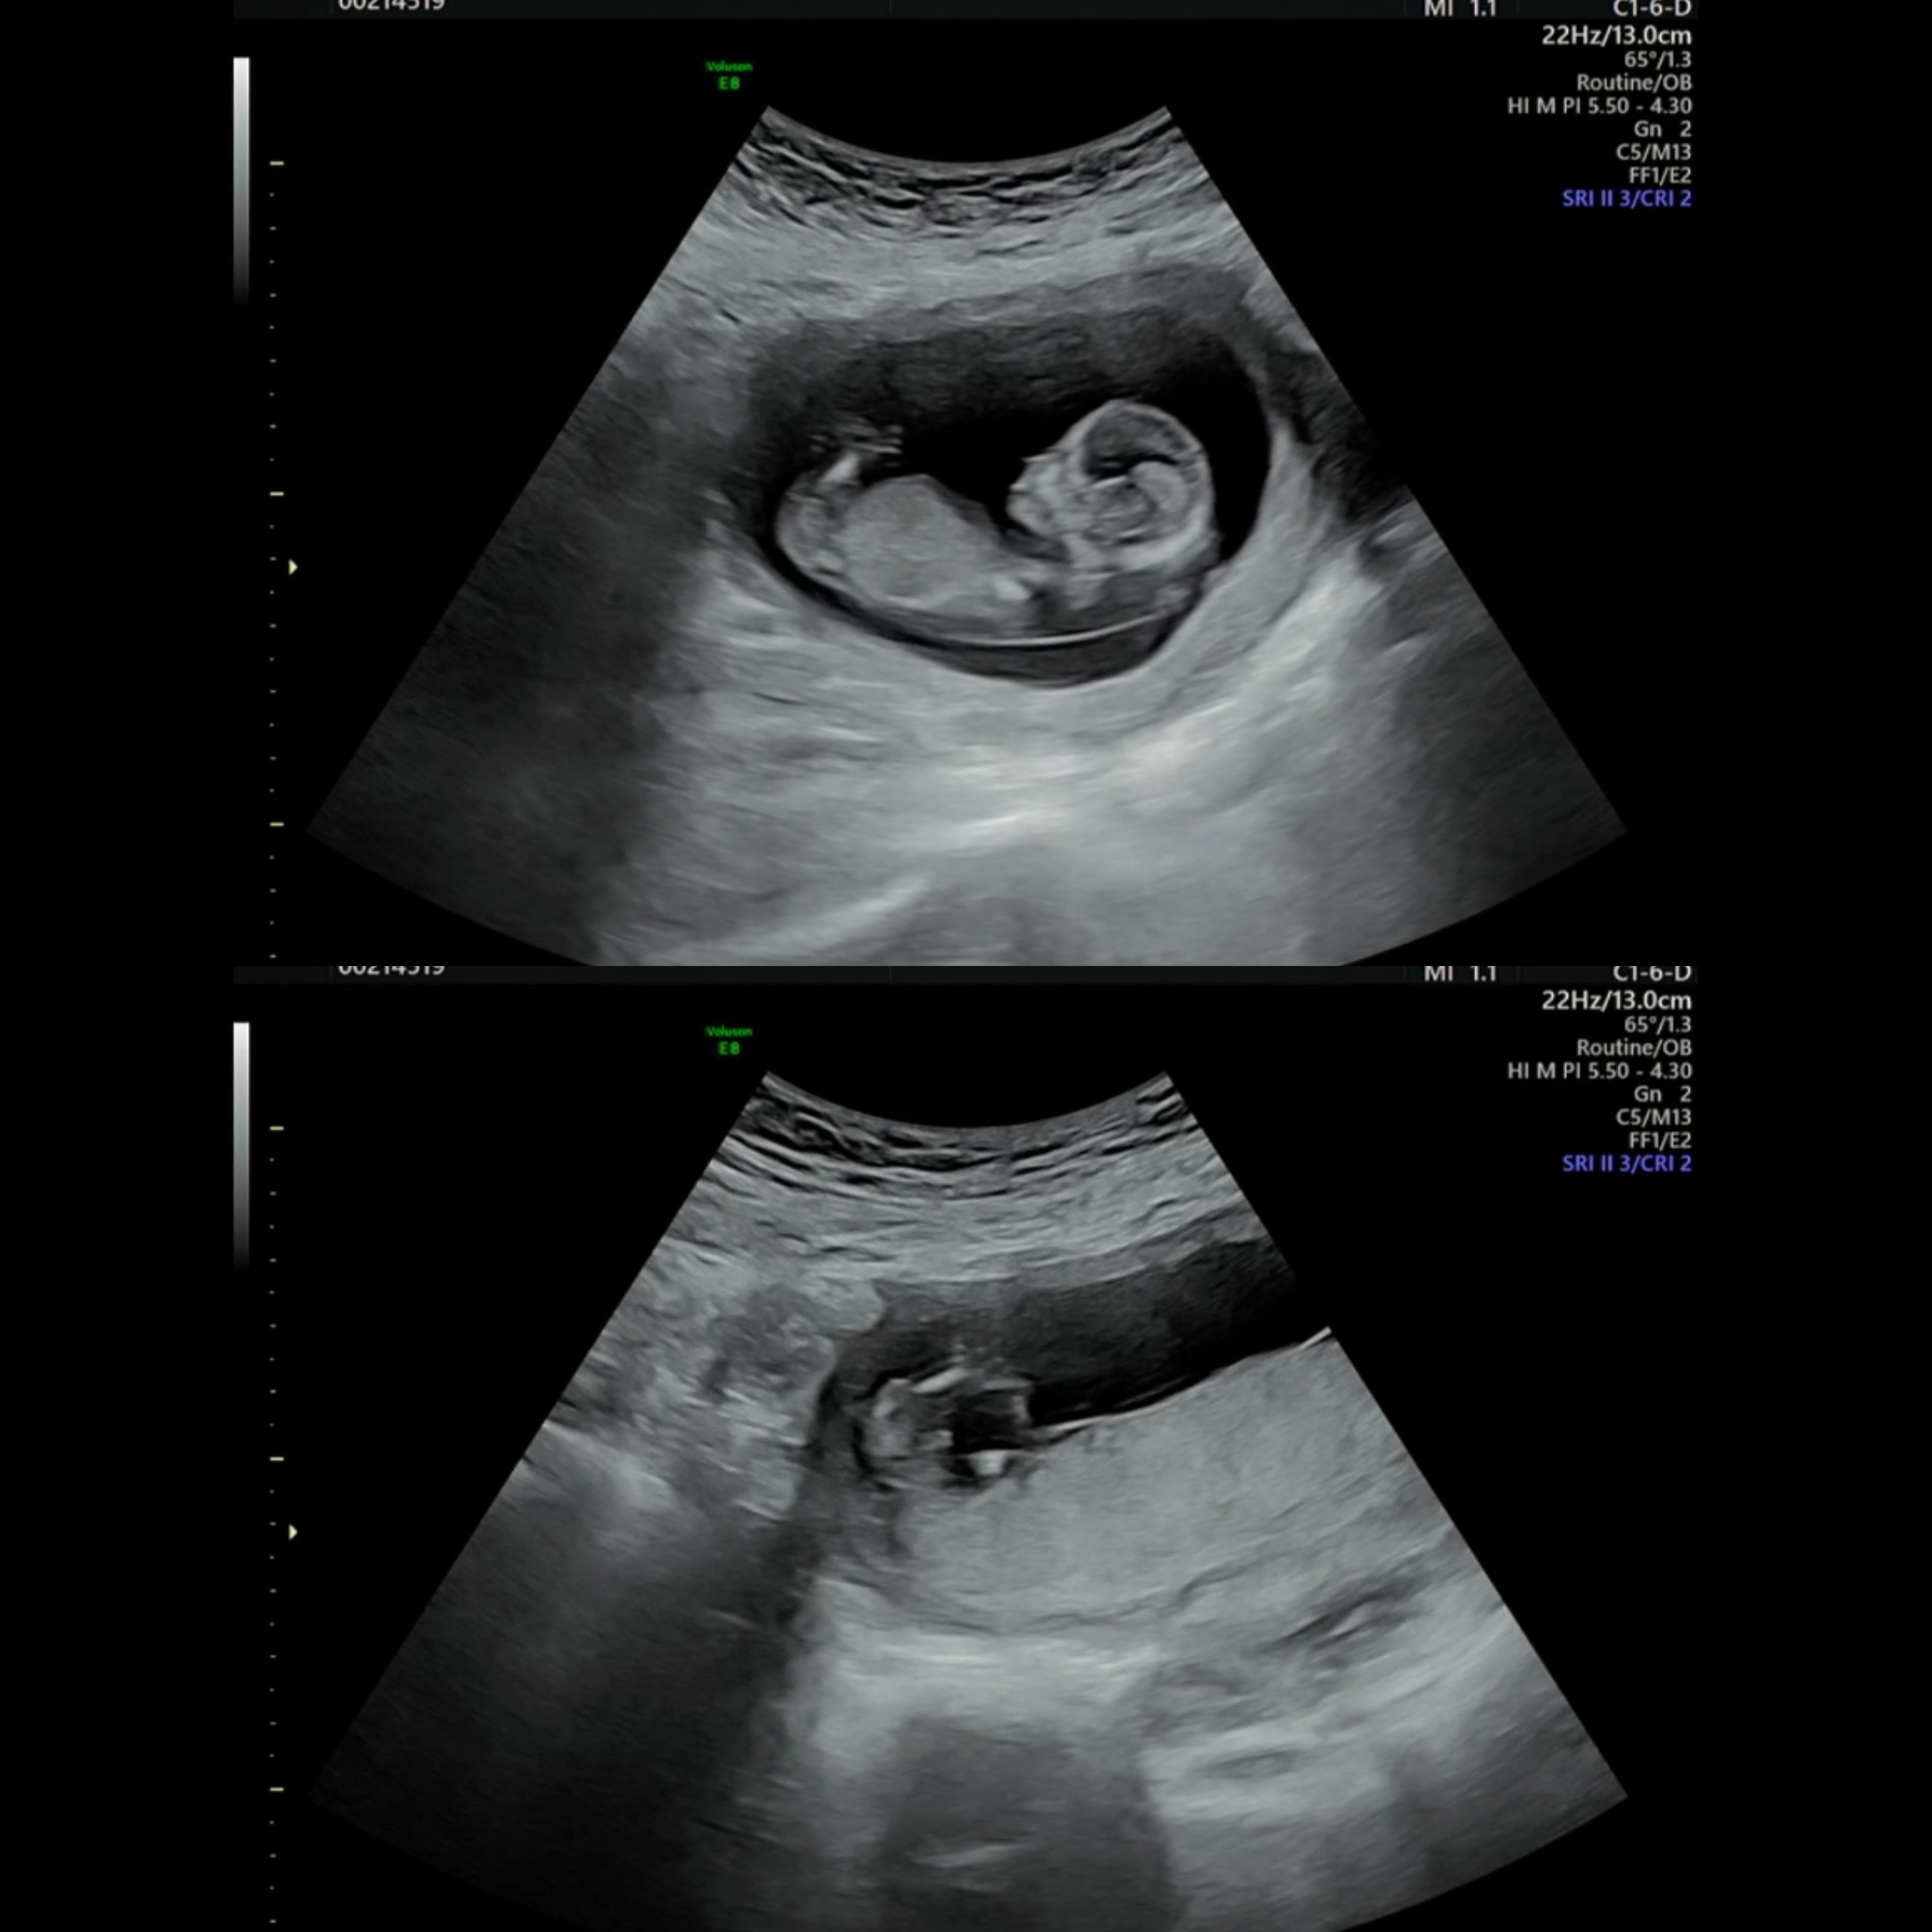

셋째..각도법 참견부탁드려요🙏

셋째까지 날줄이야.... 베이비 빌리도 다시 할줄은 상상도 못했지만ㅎㅎ 이렇게 셋째가 찾아와주었네요🥹 셋째라도 성별이 궁금한건 마찬가지라 각도법 참견좀 부탁드립니다!!! *추가 장꾸맘님도 아들같다 하시네요 아직 정확한건 아니지만 저는 아들을 바라고있어서 설레는 마음입니다💗💗 투표해주신분들 모두 감사드려요💗💗